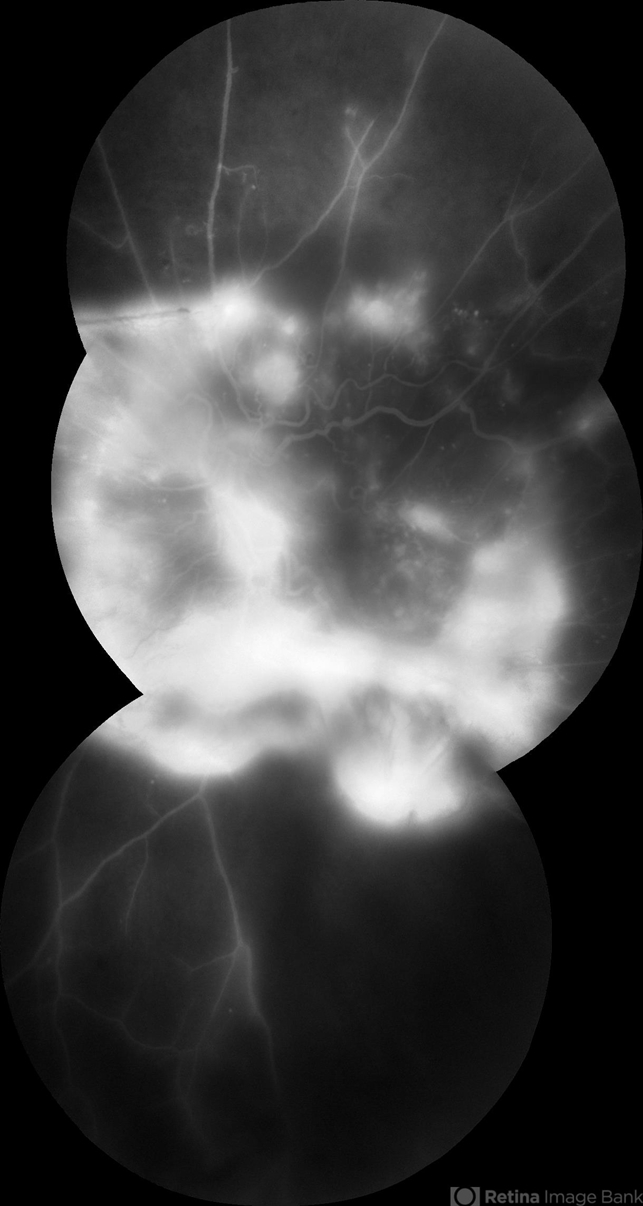

By John S. King, MD

Retina Associates, PA - Uploaded on Aug 27, 2012.

- Kristin Konecki, OcuSight Eye Care Center, Rochester, NY

- Fundus camera